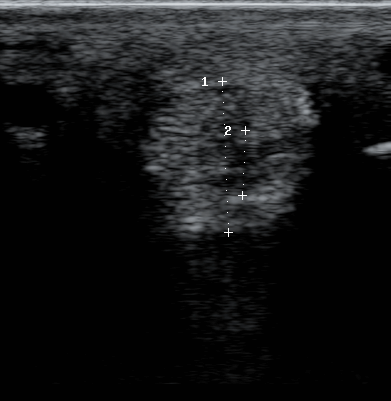

Koko oikea takajalka käytiin läpi ultralla. Elokuussa hankositeen sisähaarasta löytyi todennäköisesti laitumella syntynyt harventuma, joka on siellä tuoreen ultran perusteella edelleen. Vamma vaikuttaisi parantuneen jo kerran, mutta revenneen uudelleen ehkä tarhassa riehuessa. Kuten etenkin vasemmanpuolimmaisesta kuvasta näkee, hankositeen ulkohaara on noin puoli kertaa sisähaaraa paksumpi. Haventunut alue näkyy hyvin oikealla olevasta kuvasta. Koko jänteen pitäisi olla tasaisen harmaa, nyt keskellä oleva tumma alue kertoo vammasta. Kyseessä on kuitenkin edelleen harventuma eikä repeämä, joten sairasloma jatkuu vain joitakin viikkoja.

• Hankositeen sisähaara on selvästi paksuuntunut

• Nuljuluun kiinnityskohdassa hankoside on ok

• Kiinnityskohdan yläpuolella on selkeää harvakaikuisuutta

• Nuljuluun pinnassa lievää epätasaisuutta luupinnasa

• Jännetupen nivelneste on lisääntynyt ja jännetupessa on selkeää fibriinimuodostusta

• Muissa jänteissä ei huomauttamista